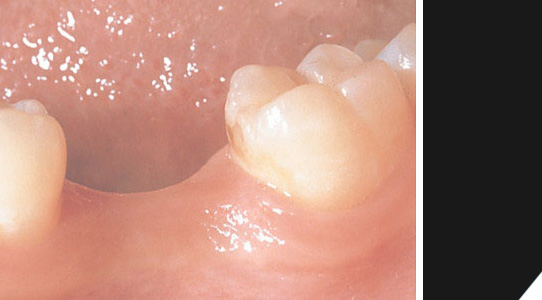

Im Unterkiefer links muß ein Zahn ersetzt werden.

Eine perfekte Krone - würden Sie den Unterschied sehen?

Allein die Röntgenaufnahme verrät, dass es sich hier um ein hochwertiges Titanimplantat handelt.